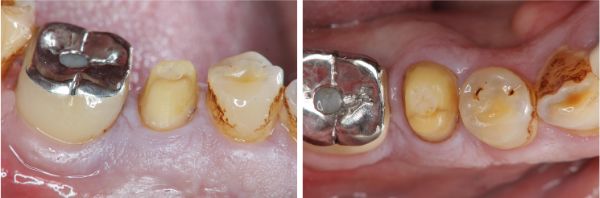

治療後口內照,患者的咀嚼機能逐漸恢復正常

治療後根尖照,透過牙冠修復受損結構,患者逐漸適應

術前、術後比較

幾年下來,這一類連續的治療,長期的癒後相當穩定,因此對於有心保留牙齒的患者,提供了另一個方法,是植牙之外的另一個重要的治療方式。